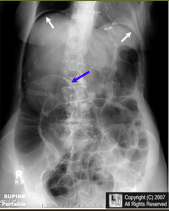

What do you see?

free air of large quantity

supine view

white arrows: crescents of air seen beneath each hemidiaphragm

blue arrows: both sides of the bowel wall are visible